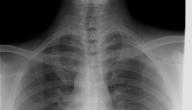

• اختبارات التصوير: إذ قد تساعد الأشعة السينية للصدر على الكشف عن كتلة غير طبيعية أو عقيدات غير طبيعية، كما أنّه يمكن أن يوفّر التصوير المقطعي المحوسب للصدر المزيد من التفاصيل، وربّما يُظهر آفات صغيرةً في الرئة قد لا تظهرها الأشعة السينيّة.